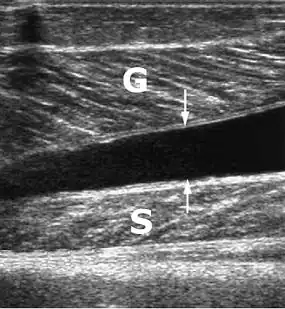

Door middel van echografisch onderzoek ('echo' of musculoskeletale echografie) is een tenniskuit duidelijk te herkennen en te onderscheiden van de rupturen. Hier twee verschillende echografische afbeeldingen van een vochtcollectie, kennelijk een hematoom (zwart, echoarm deel) tussen de musculus gastrocnemius en de musculus soleus (diepe kuitspier).

G= musculus gastrocnemius, S= musculus soleus.